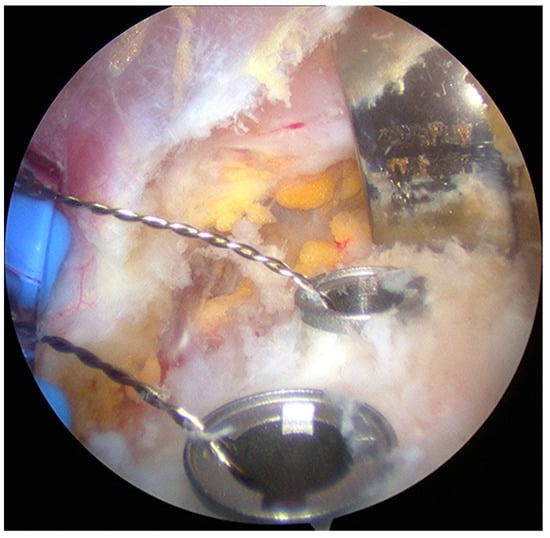

- The graft was fixed. Two holes were made through the coracoid and the glenoid using the double cannula. Graft trimming was performed with the burr (Figure 4).